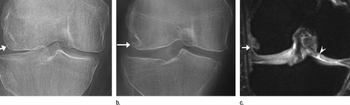

Researchers found the modality to be more proficient than radiography in identifying the hallmarks of knee osteoarthritis, but say it's still too early to recommend using tomosynthesis as a standard practice.